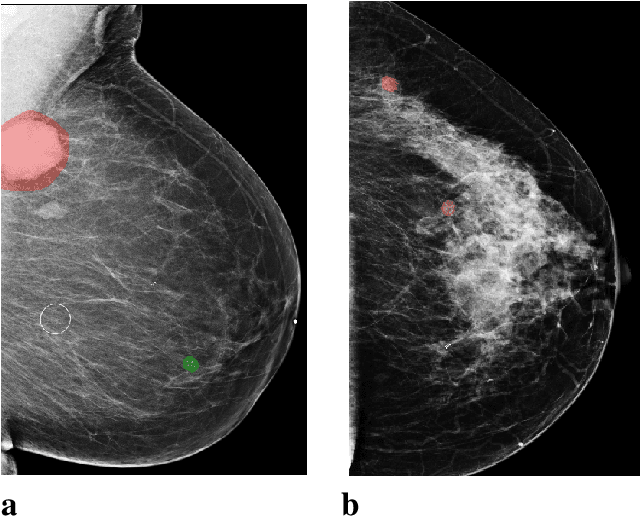

Abstract:In the last few years, deep learning classifiers have shown promising results in image-based medical diagnosis. However, interpreting the outputs of these models remains a challenge. In cancer diagnosis, interpretability can be achieved by localizing the region of the input image responsible for the output, i.e. the location of a lesion. Alternatively, segmentation or detection models can be trained with pixel-wise annotations indicating the locations of malignant lesions. Unfortunately, acquiring such labels is labor-intensive and requires medical expertise. To overcome this difficulty, weakly-supervised localization can be utilized. These methods allow neural network classifiers to output saliency maps highlighting the regions of the input most relevant to the classification task (e.g. malignant lesions in mammograms) using only image-level labels (e.g. whether the patient has cancer or not) during training. When applied to high-resolution images, existing methods produce low-resolution saliency maps. This is problematic in applications in which suspicious lesions are small in relation to the image size. In this work, we introduce a novel neural network architecture to perform weakly-supervised segmentation of high-resolution images. The proposed model selects regions of interest via coarse-level localization, and then performs fine-grained segmentation of those regions. We apply this model to breast cancer diagnosis with screening mammography, and validate it on a large clinically-realistic dataset. Measured by Dice similarity score, our approach outperforms existing methods by a large margin in terms of localization performance of benign and malignant lesions, relatively improving the performance by 39.6% and 20.0%, respectively. Code and the weights of some of the models are available at https://github.com/nyukat/GLAM